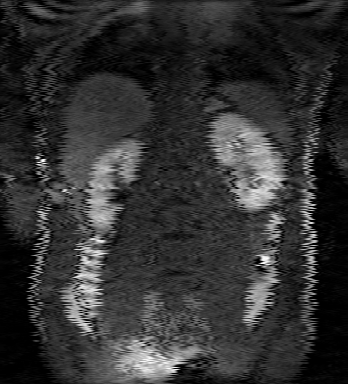

Tables 1 and 2 show our quantitative results: PSNR between the style (image we want to transfer style from) and generated image, SSIM and MS-SSIM between the content (image we want to take structure from) and generated image and finally, our proposed weighted SSIMs. For each style transfer direction and metric, our method consistently outperforms the other approaches. Figures 2 and 3 qualitatively highlight the good results of our method on 2D and 3D datasets. In addition, quantitative results on both figures show that our proposed metric preserves qualitative ordering of results for both style and content. In comparison, metrics such as SSIM struggle to accurately correlate to visual results.

(C) CW-SSIM: 0.71

(S) CW-SSIM: 0.63

(C) CW-SSIM: 0.59

(S) CW-SSIM: 0.41

(C) CW-SSIM: 0.44

(S) CW-SSIM: 0.69

(C) CW-SSIM: 0.94

(S) CW-SSIM: 0.75